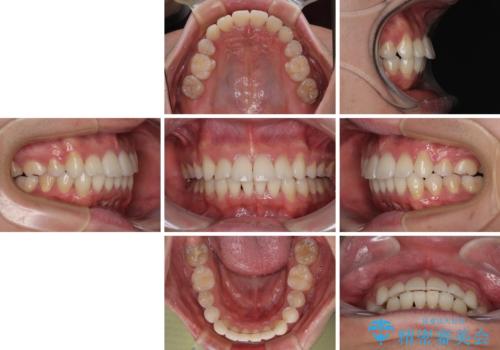

上顎のみの抜歯矯正であったため、治療期間が長期化することが予想されましたが、何とか3年弱の期間で想定通りの仕上がりで終えることができました。